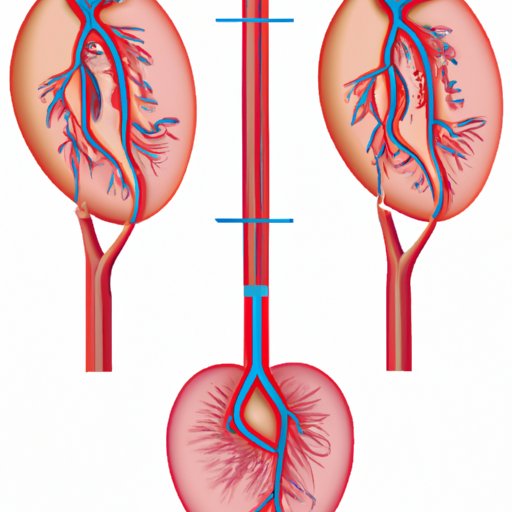

Which Artery Carries Deoxygenated Blood: Understanding the Deoxygenated Pathway and the Importance of the Deoxygenated Artery

This article explains the deoxygenated pathway and its artery, the significance of maintaining good cardiovascular health, and the pathway of blood flow. It highlights the importance of understanding the circulatory system and the role of the deoxygenated pathway in maintaining the body’s function.

Understanding the Circulatory System: Which Blood Vessels Carry Impure Blood

This article explains the role of blood vessels in the circulation of impure blood in the circulatory system. It also discusses the heart’s role in blood circulation, specific diseases that impact blood circulation, and how impure blood is filtered and transported back into circulation.